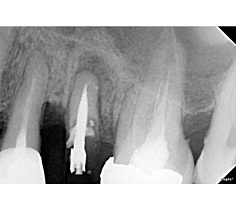

• IMAGING (производство - компания SOPRO®): продажа цифровых систем обработки изображений и стоматологического рентген оборудования;

К ассортименту компании относятся рентген аппараты, радиовизиографы, аппараты для костной хирургии, скайлеры. Группа компаний Acteon Group включает команды высококвалифицированных специалистов, работающих в 26 различных офисах по всему миру. Во всем мире врачи-стоматологи используют оборудование французского производителя. С каждым годом разработчики внедряют новейшие технологии в стоматологическую сферу и делают все возможное для того, чтобы повысить качество лечения.